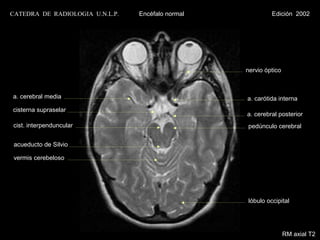

nervio óptico

a. cerebral media

tallo hipofisario

cist.supraselar

cist. interpenduncular                              cist. crural

cist. ambiens

acueducto de Silvio

cist. cuadrigeminal

vermis cerebeloso

lóbulo occipital

RM axial T1 con contraste